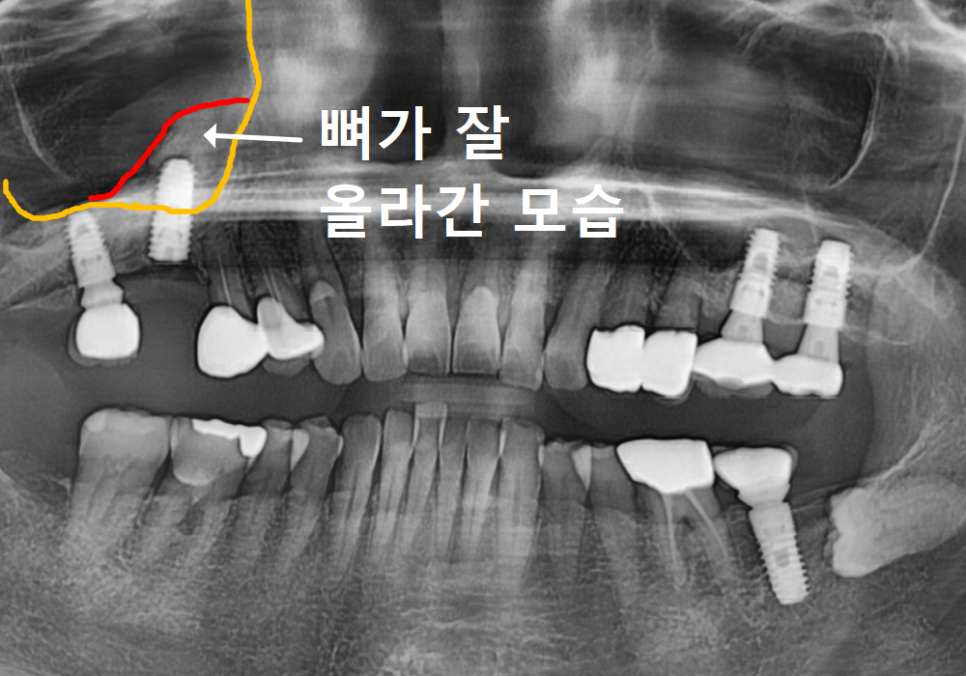

CT를 이리저리 돌려보며 뼈를 분석해 보니,

바깥쪽(볼 쪽) 뼈는 많이 녹았지만

안쪽(입천장 쪽) 뼈는 비교적 두껍고 튼튼하게 남아있었어요.

231103

그래서 뼈가 튼튼한 입천장 쪽으로

각도를 살짝 기울여

전략적으로 임플란트를 심었습니다.

231124

수술 후 CT를 확인해 보니,

원하는 위치에 정확하게,

식립된 것을 확인할 수 있었습니다.